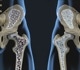

Idiopathic Juvenile Osteoporosis (IJO) is a primary condition of no known cause and is diagnosed after other causes of juvenile osteoporosis have been excluded , including primary diseases or medical therapies known to cause bone loss.

This rare form of osteoporosis typically occurs in previously healthy children just before the onset of puberty around 7 years of age with a range of 1 to 13 years and fortunately most children experience a complete recovery of bone.